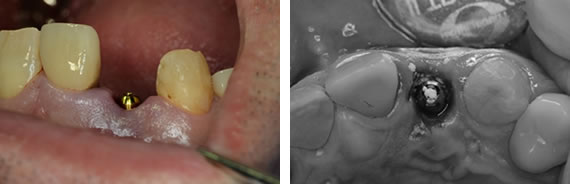

53歳 男性 数年前にセラミッククラウンを被せましたが、とれてしまったそうです。根が残ってなく、割れていたため残念ですが抜歯になりました。

残念ですが、歯が残っていないばかりか、歯根も割れています。患者さんは抜歯後、インプラント治療を選択しました。

抜歯は周りの骨を損傷しないように、普段の抜歯より細心の注意を払います。

抜歯即時のときは、相性の良いHAインプラントを使用します。

普通は歯肉を開いて、骨を明示して手術をおこなうのですが、この方法だと、歯間乳頭(歯肉の間の三角形の歯肉)とよばれる部位がなくなってしまい、被せものが審美的でないので、上の写真のように‘フラップレス’といって歯肉を開かない方法が推奨されています。

キャップの上に仮歯がすぐはいります。